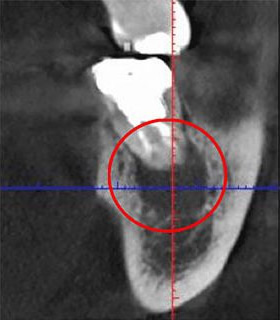

次の画像は、同じ患部をCTとレントゲンで撮影した画像です。

左の写真がCTで、右の画像がレントゲンで撮影したものです。

赤丸で囲んだところには、黒い影が見えます。ここには炎症が起こっているのですが、右の写真には影がありません。

つまり、レントゲン写真だけで診断すると、この炎症は見逃されてしまう可能性が高いということです。気がつかない間に炎症は悪化し、抜歯することになったかもしれません。当院は、このようなことを防ぐために、CTによる診断を徹底しています。